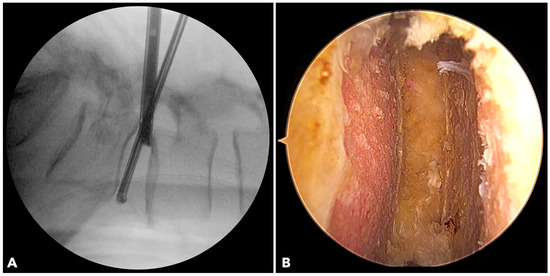

2.2.4. Disc Space Preparation

In BETLIF, direct endoscopic visualization enables radical discectomy while preserving the bony endplate. Sharp disc shavers and curettes are avoided in favor of blunt disc spreaders and specially designed endplate strippers. The endoscope is inserted into the disc space to ensure complete removal of the cartilaginous endplate (Figure 3). In MISTLIF, disc space preparation relies on tactile feedback via serial disc shavers and curettes, increasing the possibility of inadvertent endplate violation.

Figure 3. (A) The fluoroscope image shows the endoscope being inserted into the disc to evaluate the final results of disc space preparation. (B) The endoscopic photo verifies a perfect disc space preparation with no damage to the bony endplate.